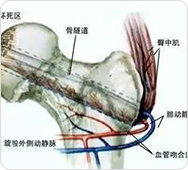

借助国家专利技术可视血堵融通术,打通股骨头血管管内各种类型淤堵损伤,解决血管供血问题,恢复股骨头血供。

通过超微痉挛减张术,对症解除髋关节周围软组织的张力,解决股骨头血管管外卡压,解决外界因素引起的供血障碍,使血管重新获得血液供应。

治疗前:通过影像,可知道股骨头周边血管分布、病灶部位,血管哪里堵塞清晰可见

治疗中:旋股内侧动脉中的血脂、血栓逐渐被疏通

治疗后:通过融通术,旋股内侧动脉逐渐恢复血供,骨关节周围血流量加快,骨细胞供血恢复正常